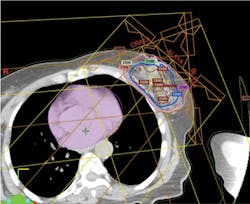

In very simplified terms, the treatment plan is accomplished by conducting computed tomography (CT) scans through the tumor area of the breast and the chest area. From this scan, a three-dimensional reconstruction of the tumor is created and transformed to a computerized image. The image is then used to plan the entrance of proton beams at multiple angles to the tumor bed area and also to determine intensity of dosage at each spot (beam scanning). Beam scanning, technically known as "pencil beam proton therapy" is a plan to "paint" a radiation dose layer by layer. Doctors and researchers at MD Anderson Cancer Center in Houston pioneered pencil beam proton therapy (see Figure 1).

Radiologists, nuclear physicists, and dosimetricists create a computerized plan that controls the proton beam so that adjacent healthy tissue and organs are unaffected by the irradiation therapy. Planning of radiation distribution is part of both photon and proton treatment plans, but proton therapy can be delivered with great accuracy since proton beams can be controlled. The computerized plan is set to designate exactly where the beam starts and stops in relationship to the lumpectomy cavity.14,15